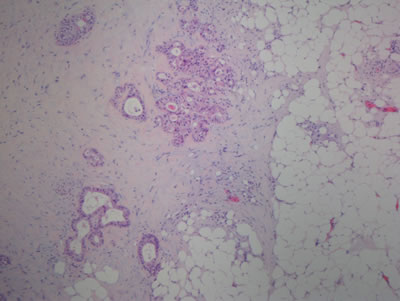

After excluding 21 patients with synchronous distant metastases, another primary malignancy or a prior history of radiotherapy to the pelvis, only 355 patients were eligible. Of these, another 15 resection specimens were missed. In the remaining 340 specimens, 30 specimens were excluded because of the bad stain and quality. Finally, a total of 310 specimens stained with hematoxy-lin and eosin could be used to determine the tumor deposits for the first round by an experienced pathologist (SYX) and the second round by another pathologist (HZZ). They were blinded to the patients’ clinical data and existing pathological outcomes. Tumor deposits were defined and evaluated based on the seventh edition of the AJCC staging manual (Figure 1). Furthermore, tumor regression grading (TRG) classification was evaluated by both pathologists together according to the current AJCC criteria (TRG 0, no residual tumor cells; TRG 1, single cells or small groups of cells; TRG 2, residual cancer with desmoplastic response; and TRG 3, minimal evidence of tumor response).

Figure 1: Tumor deposit in rectal adenocarcinoma. Tumor deposits in the perirectal fat or adjacent mesocolic fat, they away from the leading edge of the tumor, there should be no evidence of residual lymph node tissue, and the tumor deposits are within the lymph drainage area of the primary carcinoma. (H and E, 40x)